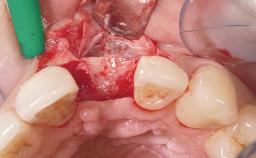

Immediate Flapless Placement of an Implant in a Maxillary Left Central Incisor Site

A 29-year-old female patient presented for treatment to replace the upper left central incisor tooth with an implant- supported restoration. The tooth had been intermittently symptomatic for the previous 12 months. The tooth had originally suffered trauma about 15 years previously. Several endodontic treatments had been performed, including an apicectomy procedure to retain the tooth. The patient was healthy and a non-smoker. She had reasonable expectations in regard to esthetic outcomes and the risk of marginal tissue recession following treatment. At medium smile, the gingival margins of the upper teeth were visible, with a display of 3 to 4 mm of the gingival margins. Gingival recession of tooth 21 and a discrepancy in the gingival levels between teeth 11 and 21 was observable during normal speech and smile.

Placement Protocol Immediate implant placement

Socket Integrity Damage to one or more bone walls

Bone Volume Damage to one or more socket walls

Esthetic Risk Medium

Risk of Complications High